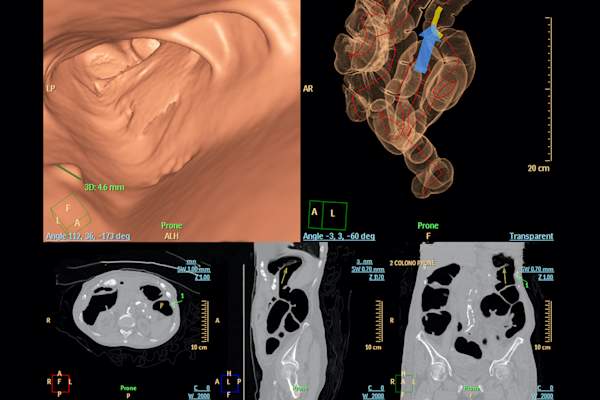

CT结肠成像

在CT结肠成像,也称为虚拟结肠镜检查,包括使用CT扫描,以寻找在结肠息肉。这还需要一个肠道准备,但没有麻醉。“这是在发现肿瘤的很好,但不是善于发现小肿瘤,鼻息肉,”桦林博士说。伊萨卡博士指出,结肠镜检查是检测比CT结肠成像的高风险息肉更好的五倍。与正常的结果,这个过程需要每五年重复。如果检测到什么异常,你就需要获得一个结肠镜检查将其删除。